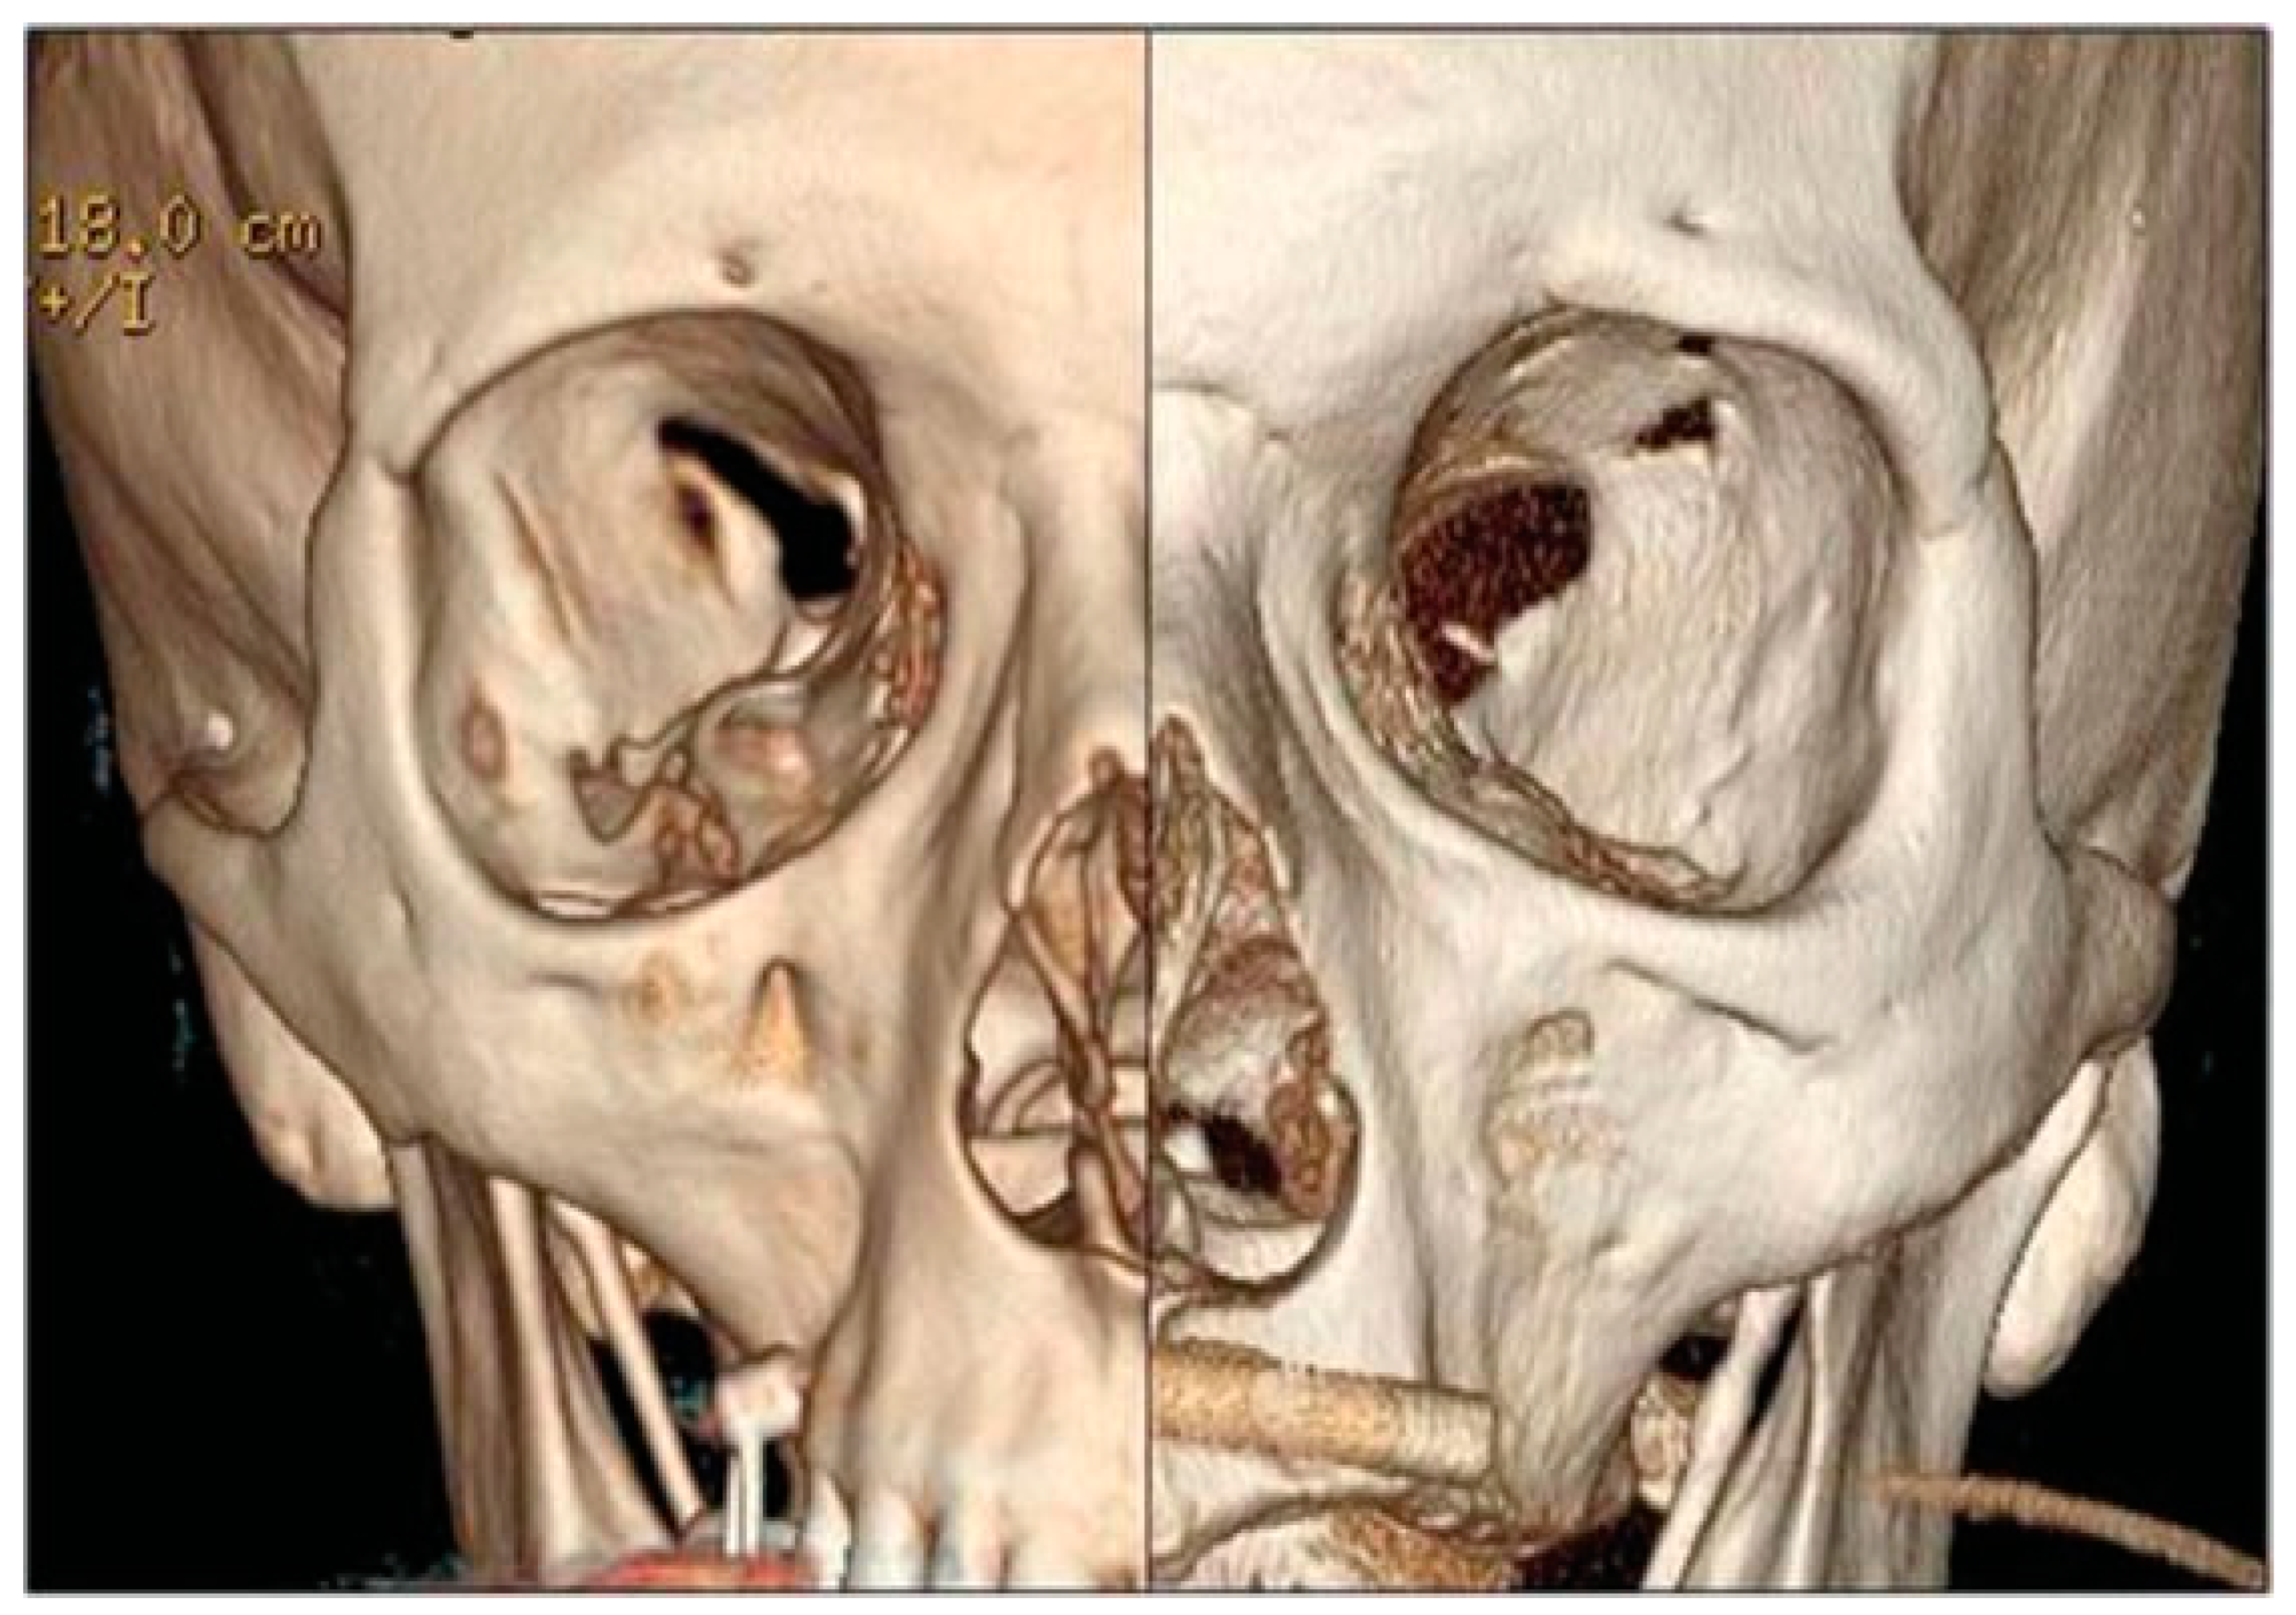

A new spiral craniomaxillofacial CT scan with coronal, sagittal, and three-dimensional (3D) reconstruction was performed the following morning. The imaging examination revealed a displacement of the lateral wall of the right SOF which was reduced in amplitude. The fracture was classified as a rare frontosphenotemporal fracture, according to Pellerin et al. [8], that is frequently associated with visual impairment (Figure 2). This pattern of fracture is characterized by the preservation of integrity of the lateral orbital wall and its whole dislocation. A thin layer of epidural blood of approximately 7 mm at the middle temporal fossa was also noticed, adjacent to the greater wing of the sphenoid bone.

Figure 2. 3D CT scan reconstruction showing four different projections of frontosphenotemporal Pellerin et al fracture pattern; note in frontal view (up right), SOF size reduction caused by medial displacement of the entire right lateral orbital wall; the black dashed line in the intracranial view (down right) shows the medial collapse of lateral orbital wall into the SOF. CT, computed tomography; SOF, superior orbital fissure; 3D, three-dimensional.